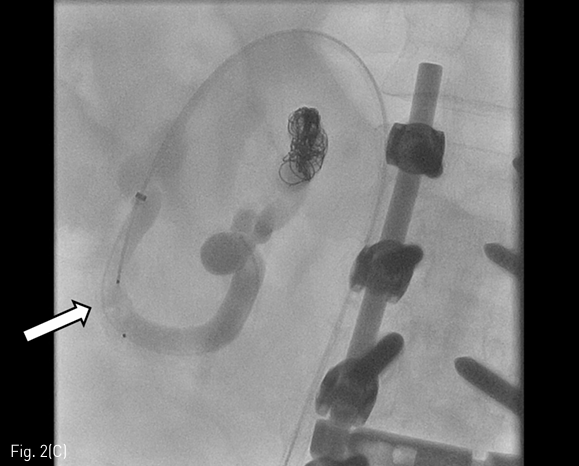

내원 3일전 시행한 전산화 단층촬영에서 간경화 소견과 함께 간문맥항진에 따른 식도정맥류와 십이지장 정맥류가 있었고 많은 양의 복수가 동반되어 있었다. 십이지장 정맥류는 주로 십이지장 제 2 부에 걸쳐 있었고 이는 상장간막 정맥(superior mesenteric vein)에서 기시하여 우측 신장정맥(right renal vein)으로 연결되는 장간막신장정맥단락 (mesenterorenal shunt)에 위치하고 있었다 (Fig. 1). 그러나 활동성 출혈(active bleeding)은 관찰되지 않았다.

Fig 1

A 55-year-old man with liver cirrhosis presents with hematochezia. Contrast-enhanced CT shows prominent duodenal varix (arrows).